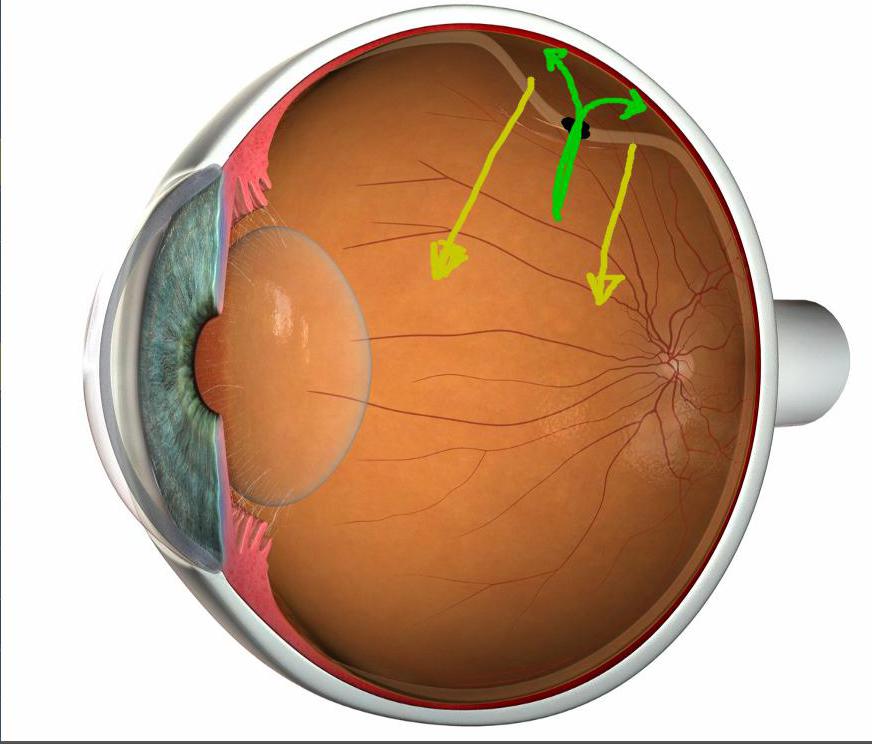

Изображения и анатомия сетчатки глаза

Раздел: Визуальный дайджест